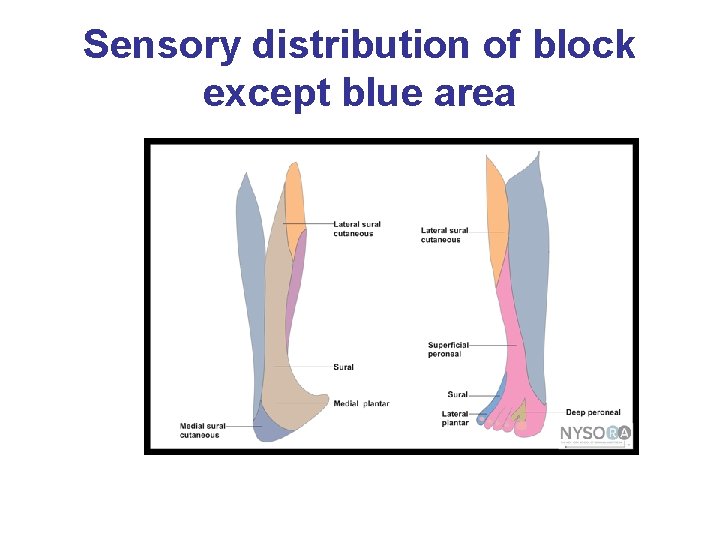

Sensory distribution of block except blue area

Popliteal Sciatic Block • Anesthetizes the entire leg below the tibial plateau except the skin of the medial aspect of the calf and foot (saphenous nerve distribution) • The popliteal block is performed on the sciatic nerve proximal to this bifurcation; about 10 cm from the popliteal crease. • Landmarks include the popliteal crease, tendons of the biceps femoris and the semitendonisimus muscles • Used for minor surgeries of the distal lower leg, foot or ankle